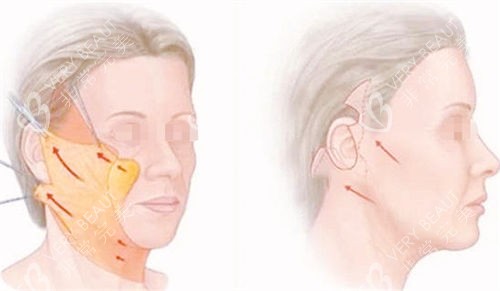

面诊时,王医生拿着我的面部 CT 片,耐心地跟我分析:“阿姨,您主要是面部 SMAS 层松弛,苹果肌下垂明显,下颌缘模糊,单纯的埋线提升或填充结果有限,做面部大拉皮 + SMAS 折叠合适。” 他还特意拿出实例照片,指着耳前位置说:“切口会藏在耳前褶皱里,愈合后基本看不见,术后十年回访,结果都很稳定,不会明显回落。” 听到 “十年不回落”,我心里的顾虑少了大半,当场就定了手术时间。

术后第七天拆线,拆开纱布的那一刻,我激动得差点哭出来。下垂的苹果肌提上去了,眼角的皱纹淡了好多,下颌线也清晰了!更让我惊喜的是,耳前的切口真的很隐蔽,不仔细看根本发现不了。王医生叮嘱我,修养期要避免做夸张的表情,按时涂祛疤药膏,三个月内不要用力揉搓面部。

如今距离手术已经过去十年,我每年都会去医院复查。王医生说我的面部状态维持得非常好,SMAS 层没有明显松弛,耳前的切口也几乎看不见了。现在的我,不仅脸上皱纹少了,整个人的心态也年轻了很多,经常跟孙女一起跳广场舞、拍短视频,生活过得有滋有味。